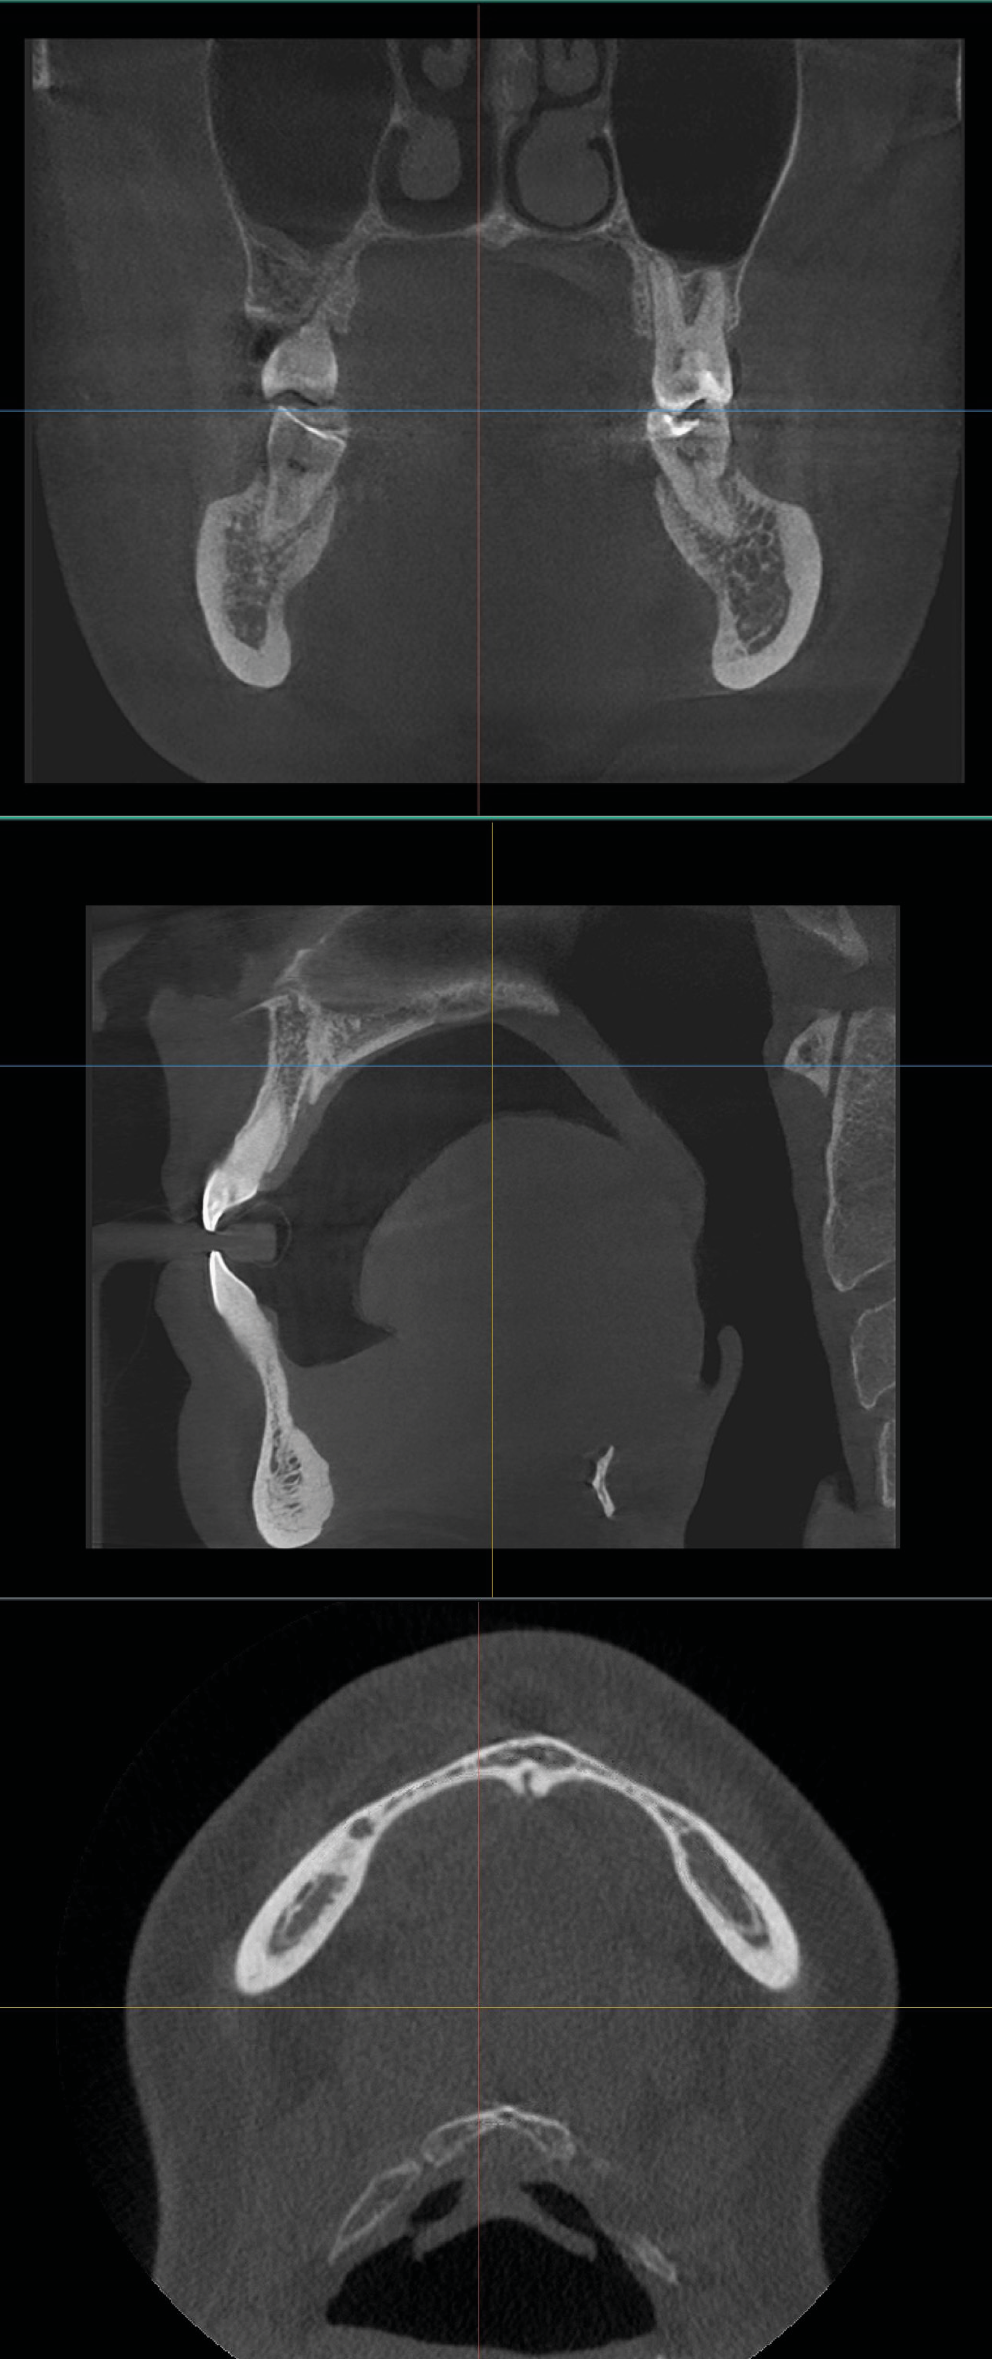

Abnormality in the position of the O-C1 joint

In addition to airway volume, the study investigated the correlation between lower airway capacity, dental abnormalities, and postural problems at a vertebral level. The deviation of the O-C1 (atlanto-occipital) joint was measured by automatically drawing a sagittal midline-using the spina nasalis and the sutura palatina media as reference points. Any displacement of the O-C1 spinous process relative to this midline was used to assess vertebral asymmetry. The methodology is illustrated in Figure 6.